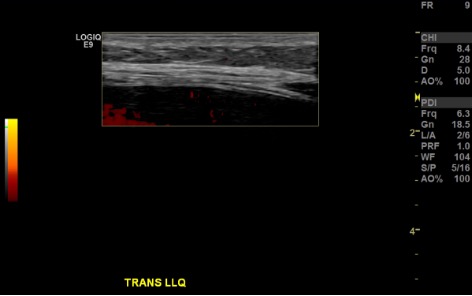

US survey — LLQ fluid pocket + Doppler

Color Doppler US of LLQ showing vessel check at planned paracentesis access site B-mode US measuring distance from skin to ascitic fluid pocket in LLQ B-mode US confirming no vessels along needle trajectory in LLQ